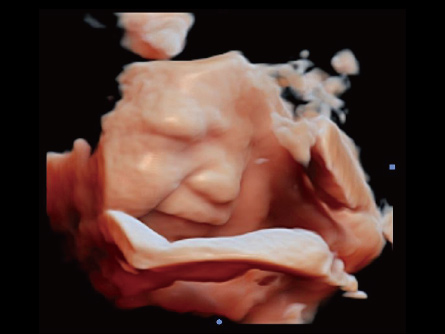

CHISON lleva la Salud de la Mujer a nuevos niveles con máquinas de ultrasonido dedicadas. Diseñadas para ginecólogos y obstetras, nuestros sistemas ofrecen una claridad sin igual en la imagen, respaldando diagnósticos seguros. Desde la atención prenatal hasta los exámenes ginecológicos, las soluciones de ultrasonido de Salud de la Mujer de CHISON proporcionan una calidad de imagen superior, mejorando la comprensión de anatomías complejas. Eleve la atención al paciente con nuestra tecnología fácil de usar y eficiente.